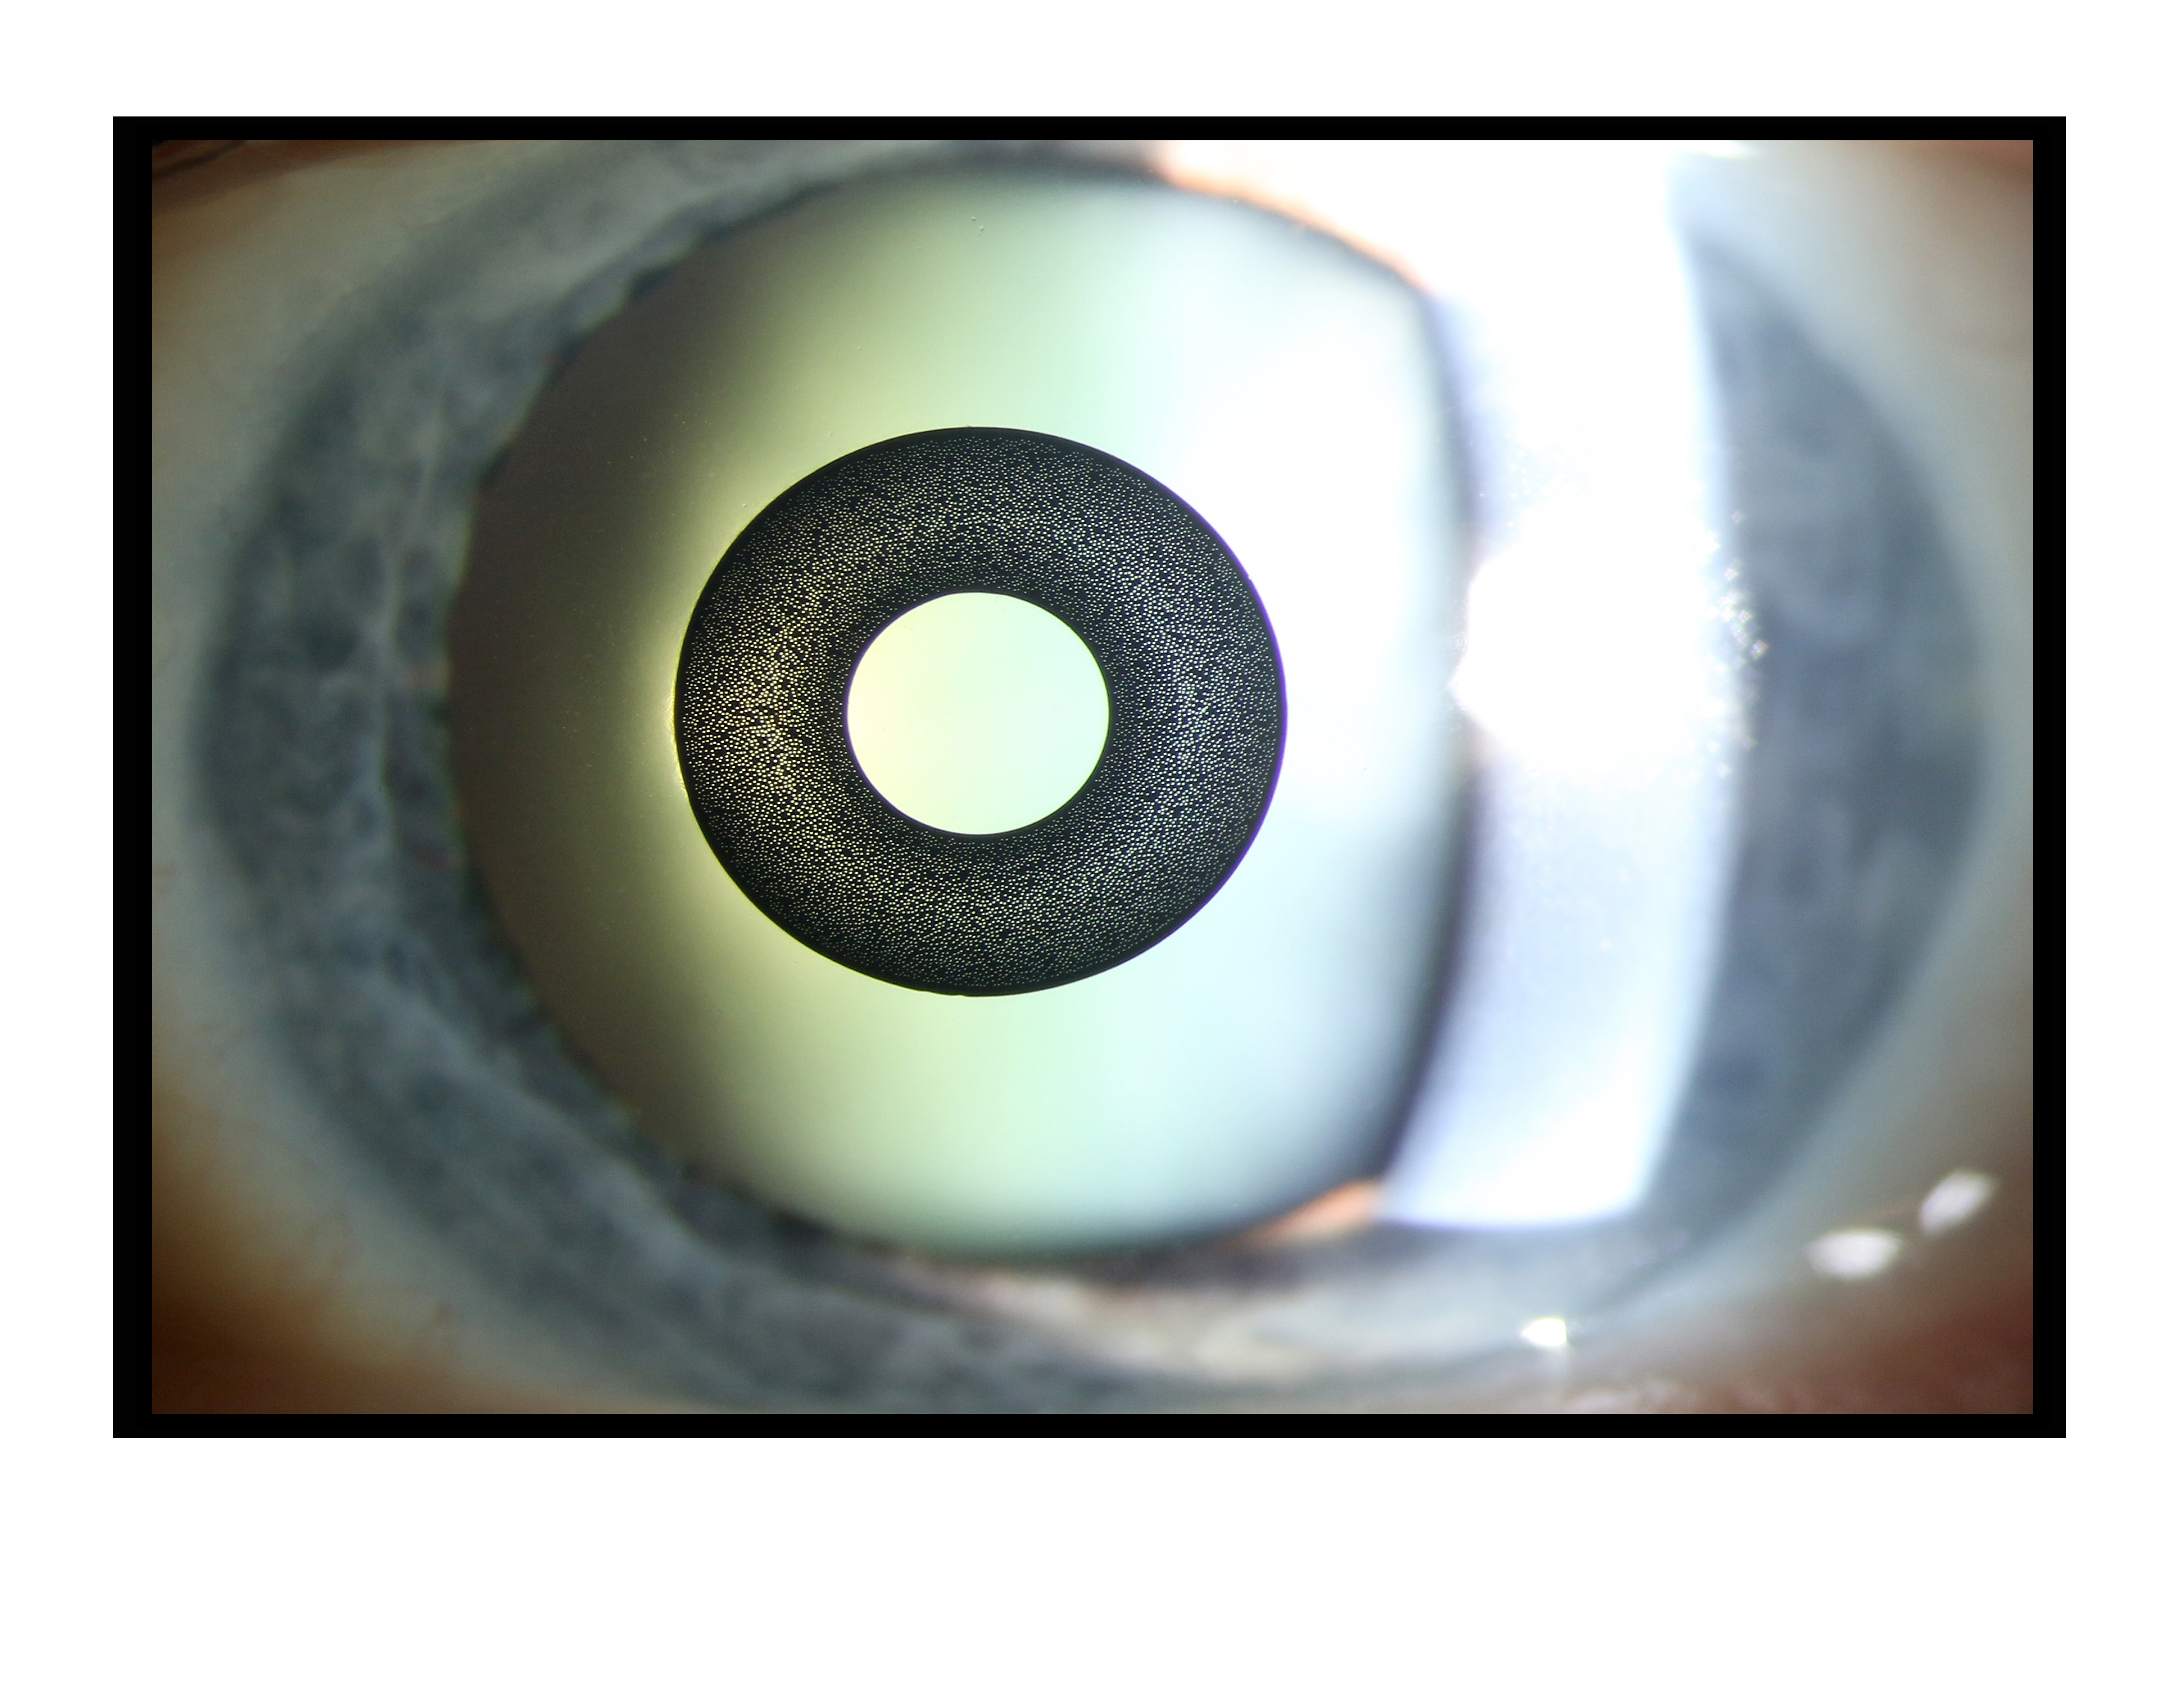

Kamra Inlay Presented by Becky Weeks, CRA, OCT-C This photograph received Second Place in the category "Slit Lamp" and was displayed in the 2024 OPS Exhibit. Filed Under Cornea OPS Photo